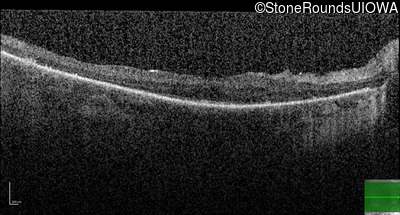

Optical Coherence Tomography - Right - 20/50

Exemplar / OCT Stack